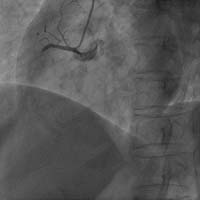

心律失常射頻消融術(shù) :包括陣發(fā)性室上性心動過速、室性心動過速、心房撲動、心房顫動的射頻消融治療。心臟先天性心臟病的介入治療:包括先天性心臟病房間隔缺損封堵術(shù)、室間隔缺損封堵術(shù)等。

Carto三維定向標測系統(tǒng)指導(dǎo)下房顫射頻消融術(shù)